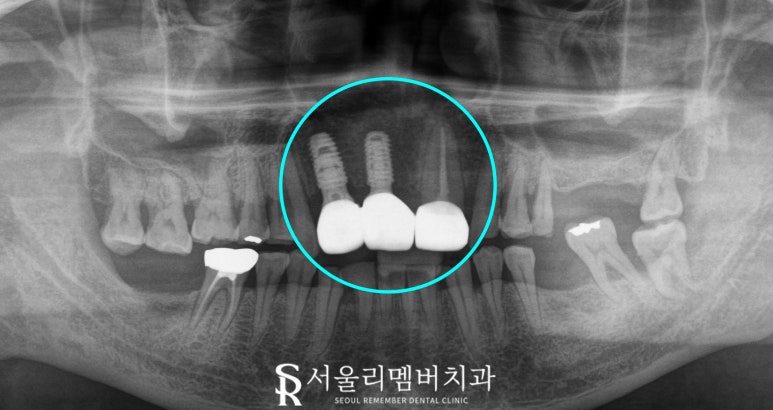

2024.12.28

모든 진료가 끝난 후,

비어있던 전치부 부위의 기능과 심미성을

회복한 모습을 보겠습니다.

서울대입구 치과 에서 보기에

임플란트와 크라운 치료를 통해

자연스러운 형태와 색이 재현되었으며,

주변과 균형과 조화를 고려하여

전체적인 치열도 맞춰진 것 같습니다.

2024.09.06 ~ 2024.12.28

비어있던 공간이 다시 잘 막아졌기에

절단 기능과 발음도 원활히 가능하실 것이고,

특히 자연치와 구분하기 어려울 정도의

색조와 투명도를 가진 보철은

환자에게 자신감을 되찾게 해줄 것이라 생각합니다.